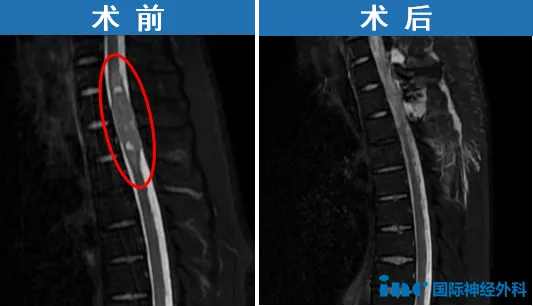

6岁确诊神经纤维瘤病,经历多次手术。2024年发现颅内及椎管多发肿瘤,伴剧烈疼痛和行走障碍。巴教授评估发现3-4个需要手术的肿瘤:胸1-胸3水平脊髓内肿瘤、腰段椎管内肿瘤、右侧桥小脑角区听神经鞘瘤及右侧大脑镰旁脑膜瘤。

鉴于病变位于不同解剖区域,需分次手术。优先处理引起胸背部疼痛的胸段脊髓肿瘤(2025年8月15日在苏州大学附属第四医院成功手术),后续再处理两个颅内肿瘤。